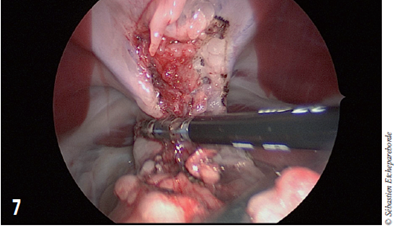

photo 7

La pince Ligasure® permet de coaguler les tissus et de les couper

Le chien a été placé en décubitus dorsal. Une approche thoracoscopique a été commencée. La masse a été libérée de ses attaches médiastinale ventrale et caudale à l’aide d’une pince à ligafusion (Ligasure®).

Bien que la masse ne soit effectivement pas invasive dans les vaisseaux sanguins, le risque de percer la capsule en manipulant la masse afin de disséquer les attaches dorsales était trop grand et la chirurgie a été convertie.